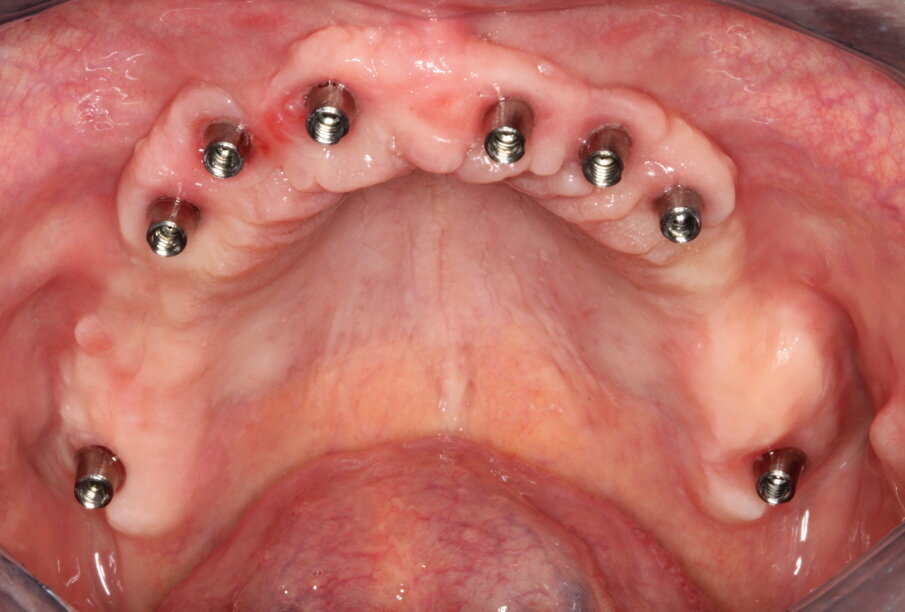

Gli impianti vengono distribuiti lungo tutta l’arcata cercando il parallelismo e limitando il più possibile i cantilever (6-7 impianti superiori e 5-6 impianti inferiori). La scelta di utilizzare i monconi dritti (grazie al parallelismo degli impianti) è da preferire in quanto quest’ultimi sono anche i più robusti e resistenti nel tempo al carico assiale; inoltre caricano l’impianto lungo il suo asse limitando i carichi disassati. Una volta elevato il lembo mucoperiosteo ed evidenziato l’osso alveolare o basale, attenzione deve essere fatta nel fare un’ostectomia riduttiva mediante una fresa a palla del diametro di 0,6-0,8 cm per creare un piano più uniforme possibile tale da formare una piattaforma d’osso alla stessa altezza, guadagnando anche spessore V-L ed uniformità. Gli impianti devono essere posizionati alla stessa altezza tra di loro e distanziati in maniera tale da favorire le manovre di igiene orale inter-implantare. Una volta posizionate le fixture sottocrestali (1-3 mm) come descritto, vanno connessi i monconi solitamente con collare mucoso di 3-4,5 mm in altezza, ponendo particolare attenzione che i tessuti molli suturati non coprano la parte di accoppiamento conometrico. Verificato il parallelismo corretto dei monconi mediante i pin parallelizzatori, siamo certi che l’accoppiamento e la disconnessione delle cappette contenute nella protesi potrà avvenire nel miglior modo possibile senza creare tensioni.

Un’impronta in silicone o digitale sulle cappette in situ accoppiate va presa alla fine della chirurgia, una volta suturati i lembi. Il paziente lascia lo studio con delle cappette provvisorie in Peek a protezione dei monconi e con la sua protesi riadattata oppure con una stampata del Brega riempita con impacco parodontale come medicamento.